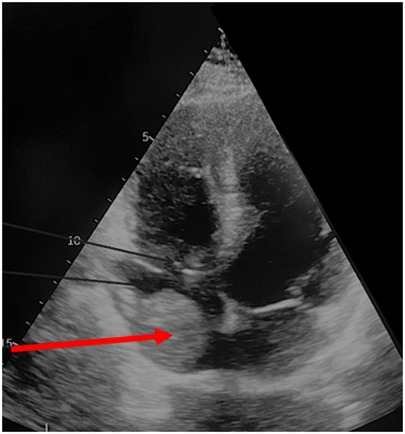

AbstractBackground:Tumor thrombus extending into the inferior vena cava (IVC) in patients with renal cell carcinoma (RCC), particularly at Mayo levels III and IV, presents a major surgical challenge. Although systemic treatments are evolving, surgery remains the mainstay of management. The role of cardiopulmonary bypass (CPB) in this setting is not clearly defined.Methods:We retrospectively analyzed 20 patients with RCC and Mayo level III–IV IVC tumor thrombus who underwent radical nephrectomy with IVC thrombectomy at our center between 2017 and 2024. Preoperative workup included MRI, contrast-enhanced CT, and transthoracic/transesophageal echocardiography. CPB was used selectively in five patients with tumor extension into and adherence to the right atrium. Postoperative complications were classified using the Clavien–Dindo system. Survival was assessed with Kaplan–Meier analysis and Cox regression.Results:Median age was 61 years (IQR 51–72), and 70% were male. Level IV thrombus was present in 60% of patients, and 40% had distant metastases. Median operative time was 370 minutes and median blood loss was 2,500 mL. Postoperative complications occurred in 20% of patients, with one in-hospital death (5%). Median hospital stay was 11 days. The 1-, 3-, and 5-year overall survival rates were 66.7%, 41.6%, and 34.6%, respectively. Distant metastases were associated with lower survival (HR 2.48; p = 0.005), while immuno-targeted therapy improved outcomes (HR 0.69; p = 0.035).Conclusion:Radical nephrectomy with IVC thrombectomy in patients with advanced tumor thrombus can be performed safely with good long-term outcomes in selected cases. Careful preoperative imaging, intraoperative echocardiography, and the selective use of CPB are key to minimizing risks. These findings support a tailored surgical approach based on thrombus level and clinical condition. Further prospective studies are needed to refine surgical indications and clarify the role of systemic therapy.